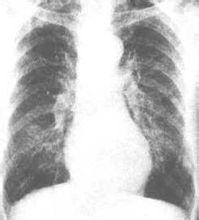

X線徵象

單純型慢性支氣管炎,X線檢查陽性,或僅見兩肺下部紋理增粗,或呈索條狀,這是支氣管壁纖維組織增生變厚的徵象。若合併支氣管周圍炎,可有斑點陰影重疊其上。支氣管碘油造影,常可見到支氣管變形,有的狹窄,有的呈柱狀擴張,有的由於痰液瀦留,呈截斷狀。由於周圍瘢痕組織收縮,支氣管可併攏呈束狀。有時可見支氣管壁有小憩室,為粘液腺開口擴張的表現。臨床上為明確診斷,透視或攝平片即可滿足要求。支氣管碘油造影只用於特殊研究,不作常規檢查。

3.X線檢查 早期可無明顯改變,反覆急性發作者可見兩肺紋理增粗紊亂呈網狀或條索狀及斑點狀陰影,以下肺野為明顯,此系由於支氣管管壁增厚、細支氣管或肺泡間質炎症細胞浸潤或纖維化所致。